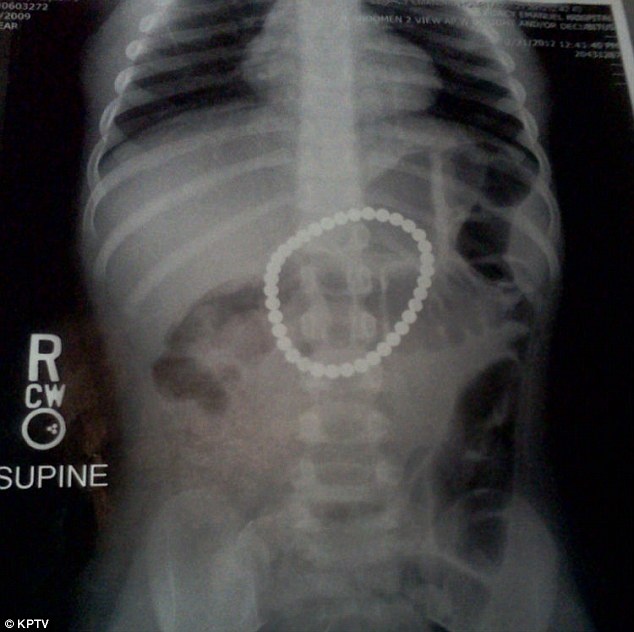

Όταν το κοριτσάκι άρχισε να πονάει πολύ, οι γονείς της την έτρεξαν αμέσως στο νοσοκομείο όπου και της έγινε ακτινογραφία. Εκεί διαπιστώθηκε ότι το στομάχι της περιείχε κάτι σαν κολιέ. Φυσικά δεν επρόκειτο για κολιέ αλλά για 37 στρογγυλά μαγνητάκια που λόγω έλξης, είχαν σχηματίσει έναν κύκλο και αυτός έμοιαζε πράγματι με κολιέ.

Δυστυχώς, τα πράγματα ήταν χειρότερα από ό,τι θα περίμεναν οι γονείς της καθώς σύμφωνα με τους γιατρούς, οι μαγνήτες που είχε καταπιεί η Πέιτον, είχαν τρυπήσει ζωτικά της όργανα. Η μόνη λύση ήταν το χειρουργείο ώστε να μην κινδυνεύει η ζωή της.